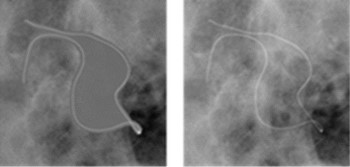

・フォトンカウンティング型X線検出器を用いた摘出乳房組織における乳癌検出能に関する研究

デンスブレストにおいて従来の乳房撮影装置による乳癌の検出限界が懸案となっている。乳癌検出におけるフォトンカウンティング型X線検出器の有用性を検討することを目的とした。藤田医科大学病院にて乳房温存術または乳房全切除術が実施された20症例を対象とし、フォトンカウンティング装置で得られた画像に、感度補正を行い、エネルギー積算画像を自作プログラムにより作成した。検出器の感度補正により、カウント画像のアーチファクトを除去することができた。また、各エネルギー帯域のカウント画像の重み係数を調整することで、画質を向上させることができた。臨床用乳房撮影装置との比較評価については、重み付けエネルギー積算画像とカラー表示による物質弁別画像を併用することで、臨床用乳房撮影装置よりも評価結果が優れる症例があった。